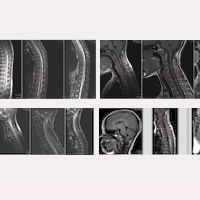

Fig.1. Preoperative images of Case 19475: magnetic resonance scans from the end of 2017 – brain, cervical, thoracic and lumbo-sacral.

In her preoperative MR images from 2017 (Fig.1), the following findings, among others, could be observed:

- Descent of the cerebellar tonsils between the lower edge of the posterior arch of C1 and the upper edge of the posterior arch of C2. Mild dilation of the fourth ventricle.

- Syringomyelic cavity at C4-D1, highly dilated.

- Cervical and thoracic ischaemia-oedema, extending to the conus medullaris (pre-syringomyelia).